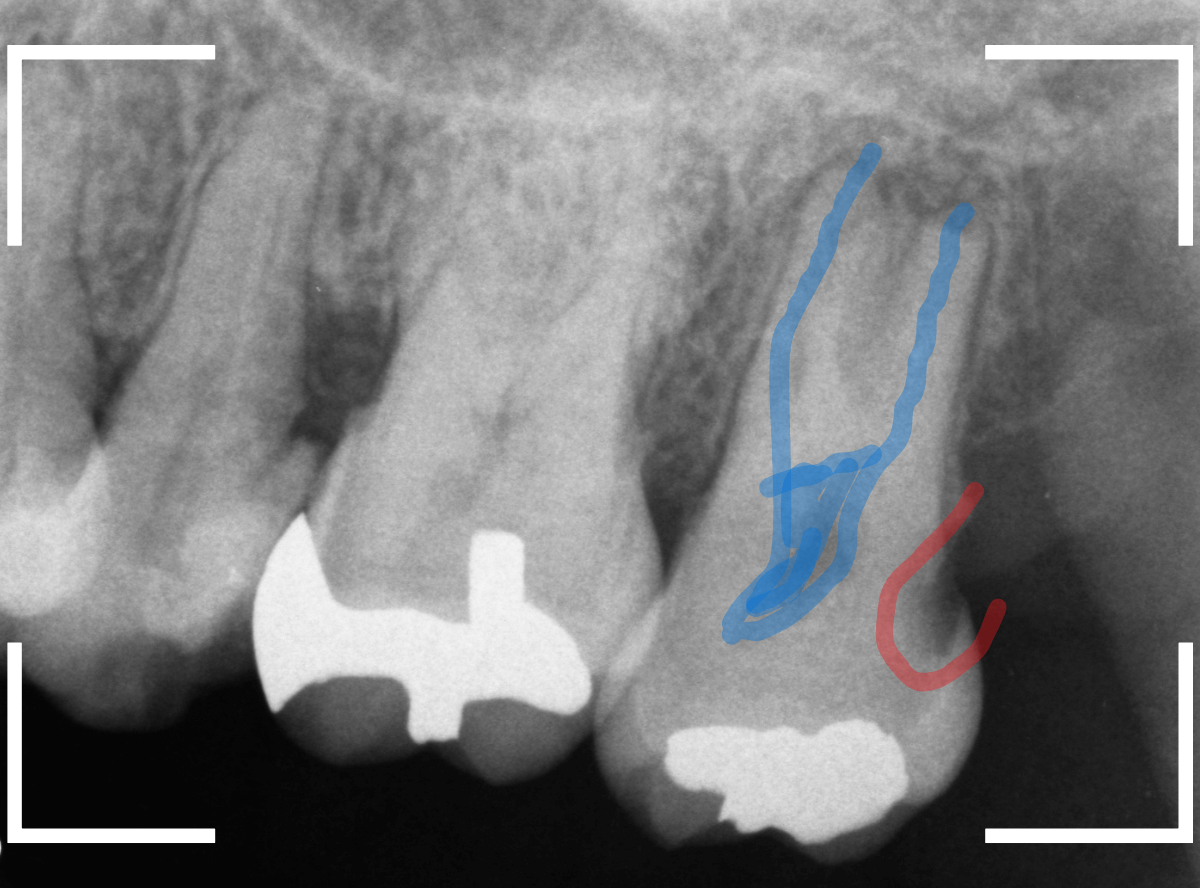

「下の一番奥の歯が痛い」という訴えで来院された患者さんの例です。

一見では、特に問題ないように見えます。

レントゲン写真で確認します。

青いラインが歯の神経、赤いラインが虫歯です。

歯の奥の見えない部分から、大きな虫歯になっているのがわかります。

神経を除去しなければいけないかもしれないくらいの虫歯です。